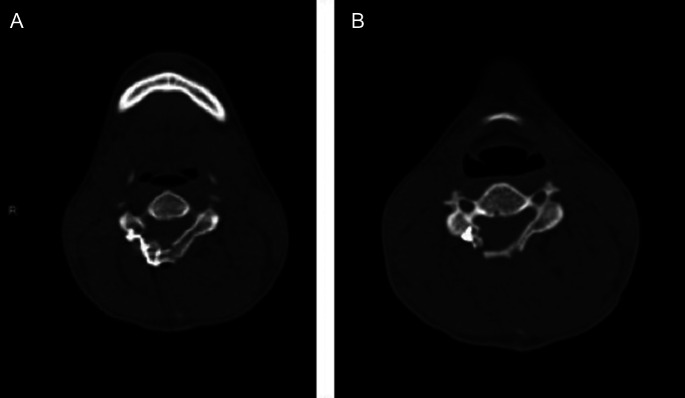

脊髓型颈椎病是一种很少报道的儿童运动或神经肌肉疾病患者。我们在此报告一例罕见的脊髓型颈椎病,患者为一名14岁的健康男孩,他之前是一名接受颈椎椎板成形术的患者,这是由于颈椎管狭窄导致的多节段椎间盘突出。患者提出了痉挛和共济失调的步态与以前的诊断挑战的诊所。磁共振成像显示颈椎退行性改变主要表现在C3-C4和C4-C5水平,t2加权图像上伴有椎管狭窄和中央高信号索异常。采用C3-C4开门椎板成形术。手术后神经症状和体征显著改善。随后,颈椎计算机断层扫描和磁共振成像显示,在5年的随访中,颈椎脊髓得到了良好的减压,活动范围得以保留。我们的结论是,尽管这种情况非常罕见,但在诊断青少年患者步态和平衡障碍时应考虑颈椎病。

Cervical myelopathy is a condition that is rarely reported in pediatric patients who have movement or neuromuscular disorders. We, herein, present a rare case of cervical myelopathy observed in a 14-year-old patient, who was previously a healthy boy treated with cervical laminoplasty, which was caused by cervical spinal canal stenosis based on multiple level disc herniation. The patient presented to the clinic with spastic and ataxic gait with previous diagnostic challenges. Magnetic resonance imaging showed cervical degenerative changes mainly marked at the C3-C4 and C4-C5 levels, along with canal narrowing and a central high signal cord abnormality on T2-weighted images. A C3-C4 open-door laminoplasty surgery technique was performed. The neurological symptoms and signs improved dramatically following surgery. Subsequently, cervical computed tomography and magnetic resonance imaging showed good decompression of the cervical spinal cord during the 5 years of follow-up with the preservation of the range of movement. We concluded that though it is pretty rare, cervical myelopathy should be considered in diagnosing adolescent patients with gait and balance disorders.